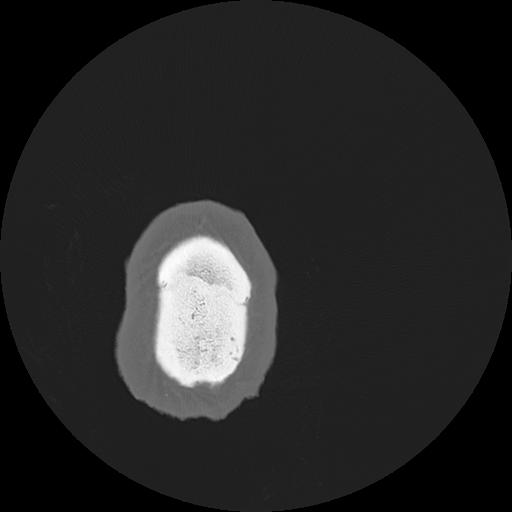

7 HUESO,,Vol,0.5,HUESO,,